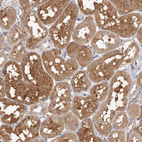

Immunohistochemistry analysis in human lymph node and skeletal muscle tissues using HPA029606 antibody. Corresponding LAP3 RNA-seq data are presented for the same tissues.